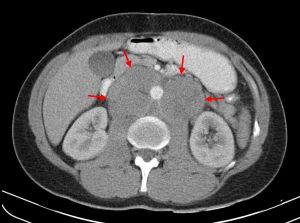

PET-CT는 특히 범내시경 검사 전에 안내 도구로 사용될 때, 두경부의 잠재적인 원발성 암을 식별하는 데 도움이 되며, 최대 60%의 경우 치료 관련 임상 결정을 유도할 수 있음이 입증되었다.[27]

세침 흡인 세포 검사(FNAC)는 악성 경부 림프절병증의 조직병리학에서 각각 81%와 100%의 민감도와 특이도를 갖는다.[27] PET-CT는 특히 범내시경 검사 전에 안내 도구로 사용될 때, 두경부의 잠재적인 원발성 암을 식별하는 데 도움이 되며, 최대 60%의 경우 치료 관련 임상 결정을 유도할 수 있음이 입증되었다.[27]